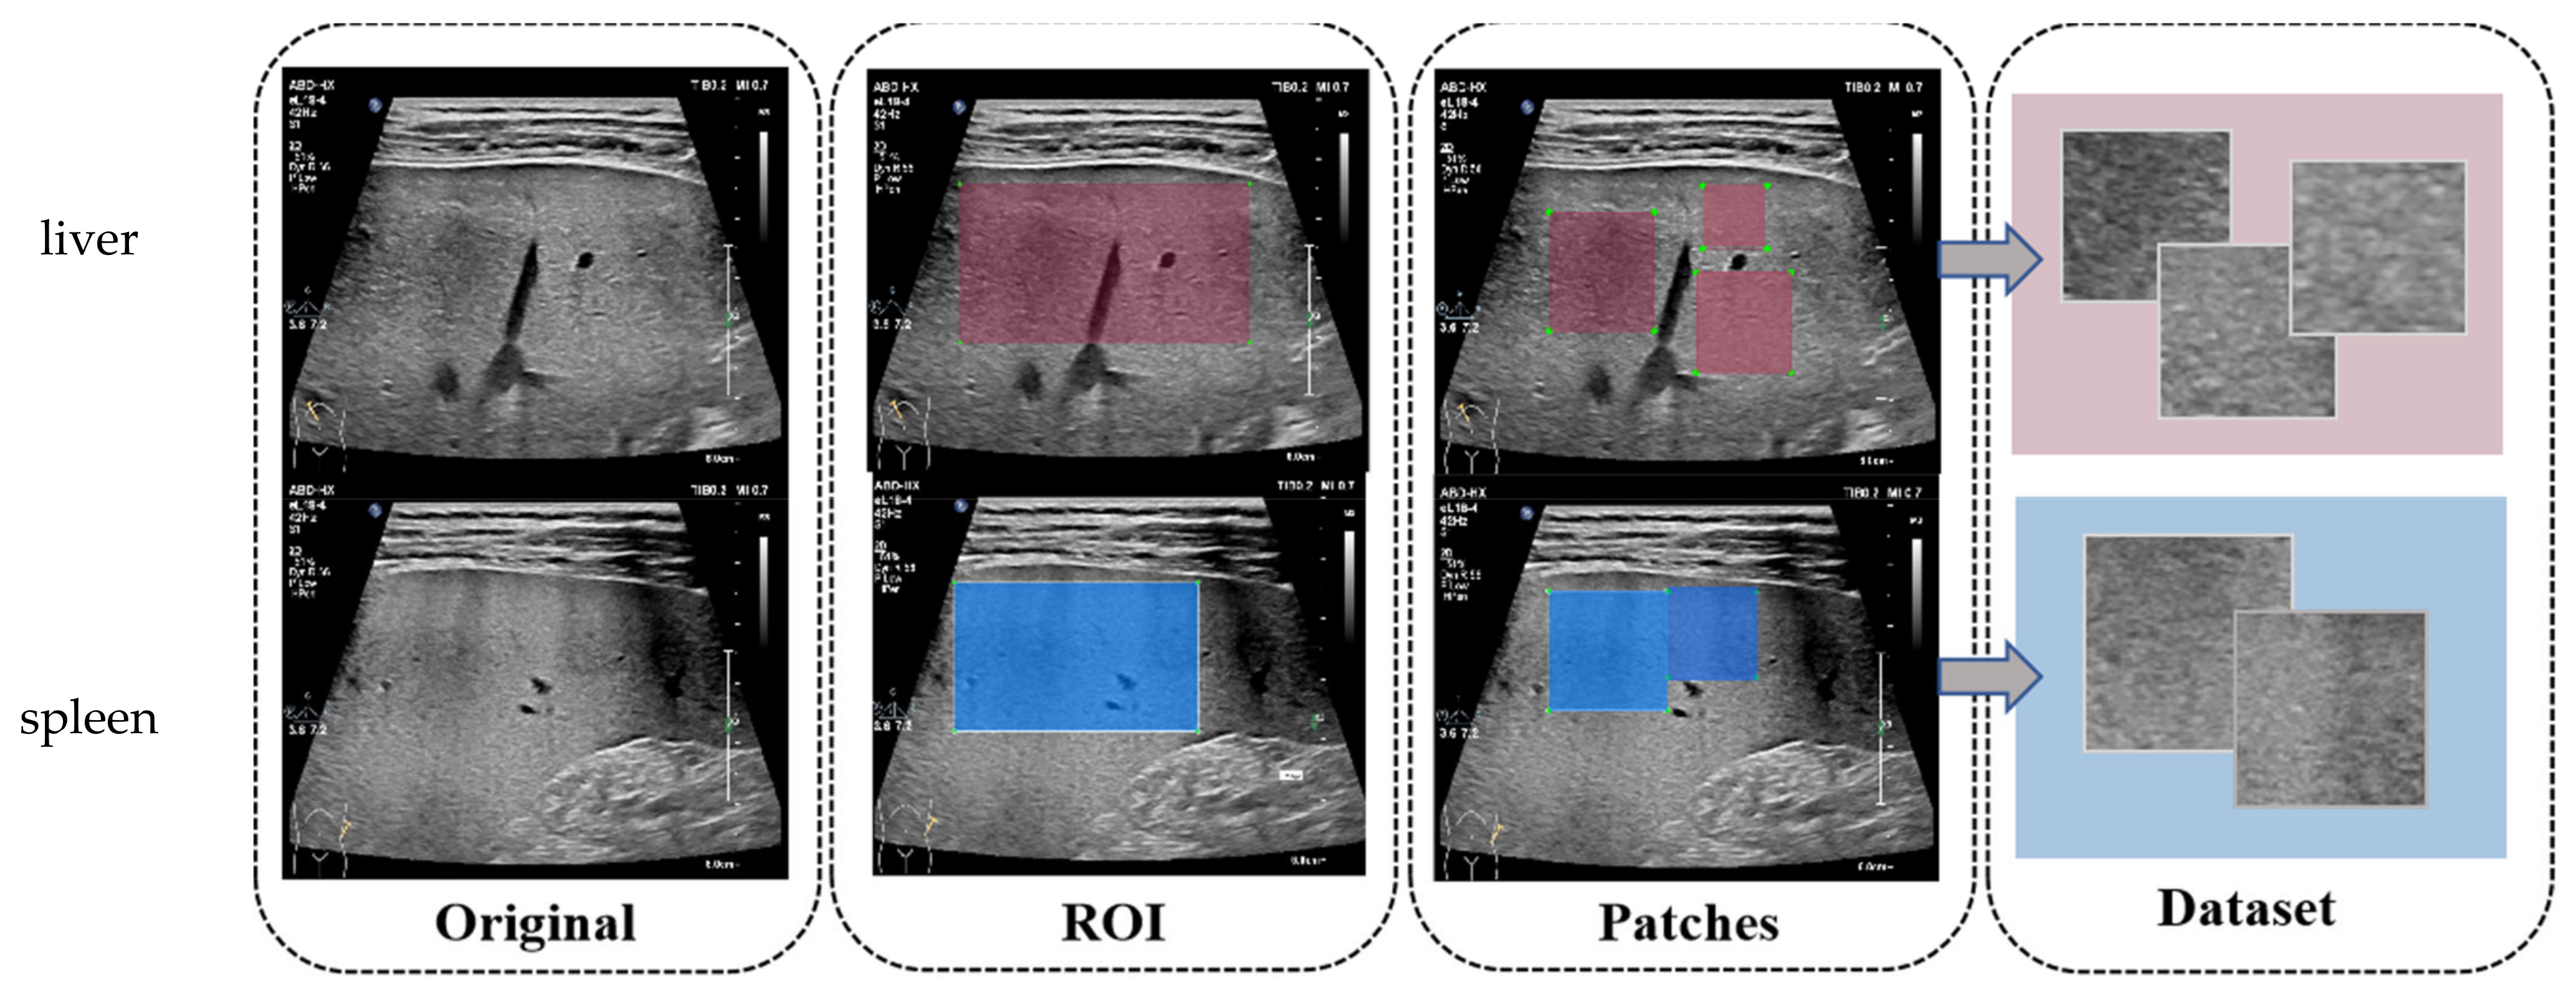

2.3. Patch-Based Image Processing